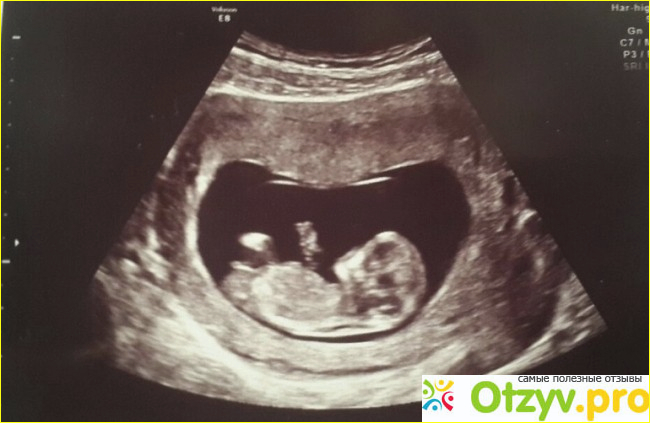

На сегодняшний день наиболее актуальной процедурой становиться обследование в гинекологии, для беременных, на выявления патологий плода на ранних сроках, ещё в утробе матери. Всего за период беременности женщина проходит три скрининга, на определения синдрома Дауна, синдрома Эдвардса, и дефекты нервной трубки. В группу риска попадают женщины после 35 лет и до 17-18 лет, родители с предрасположенностью к заболеваниям, если большая разница между отцом и матерью ребенка и так далее. Генетический скрининг - это очень важные процедуры, так как во время обследования действительно можно определить патологии плода до 90 % точности. Но к сожалению результаты не всегда достоверны. После появления ребенка на свет ему приходится проходить так же ряд скринингов. Которые помогут определить генетические, врожденные заболевания и проверить его слух. На сегодня это обязательные процедуры для всех грудничков. Это очень хорошо, ведь находясь в стационаре вам сделают все необходимые процедуры!!!

Из личного опыта скажу, что я проходила процедуру скрининга во время беременности три раза, которая достоверно показала все необходимое. Я не жалею, что проходила данные процедуры. Единственный их минус в стоимости, ведь процедура не одна из дешевых, но она стоящая. Так, что мой отзыв про скрининг будет конечно же положительный, и я бы рекомендовала проходить данную процедуру, особенно беременным девушкам. Думаю мой отзыв о скрининге будет полезен вам при выборе подобного ряда процедур.